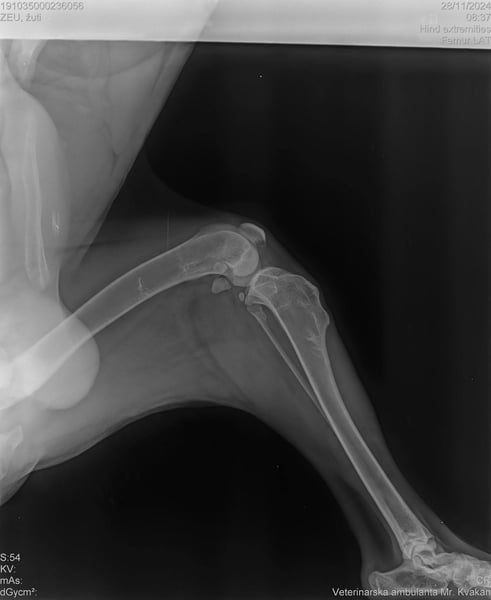

Eines seiner Hinterbeine war gebrochen, es wuchs wieder zusammen, aber es ist nun schwächer als die anderen und es fällt ihm nicht ganz leicht auf dem Bein aufzutreten. Doch Elijah hält sich wacker und sucht nun dich: einen Freund, der ihm Sicherheit und Geborgenheit bietet und ihm zeigt, wie schön das Leben ist.